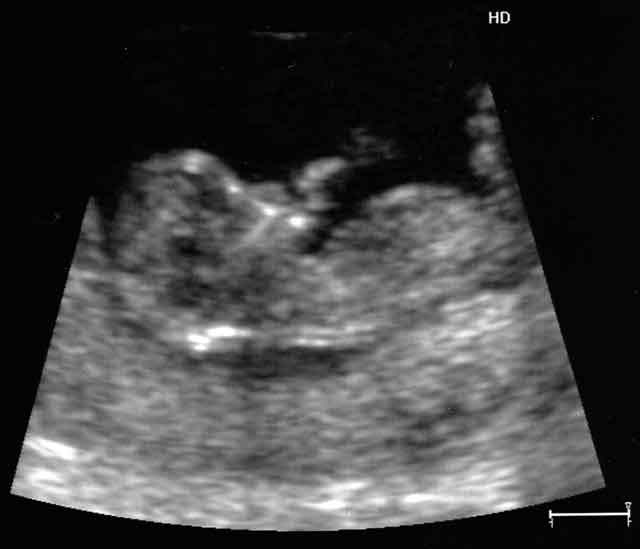

Little FunkyZorro - 12 Weeks, and thumb sucking already.